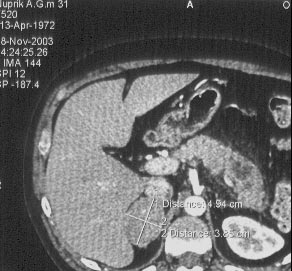

Рис. 6. На Рис. 6 и 7 демонстрируется роль поворота пленки при сканировании. На данном изображении выраженная полосатость, особенно хорошо заметная на фоне печени. Этот артефакт объясняется построчной распечаткой изображения на пленку принтером (в данном случае на термопринтере AGFA DryStar3000).